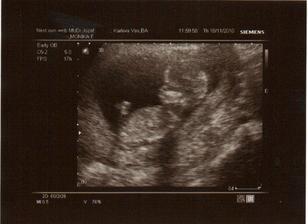

✿♥♥♥♥Bude to dievčatko!!!!! ♥♥♥♥✿

Bude to Stella 🙂

Krasne foto dufam ze ti uz je lepsie mojko 🙂